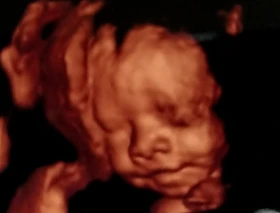

Para la CIDH una ecografía es un crimen mayor que el aborto

La Comisión Interamericana de Derechos Humanos (CIDH), que abiertamente se ha manifestado a favor de la despenalización del aborto en diversos países,...